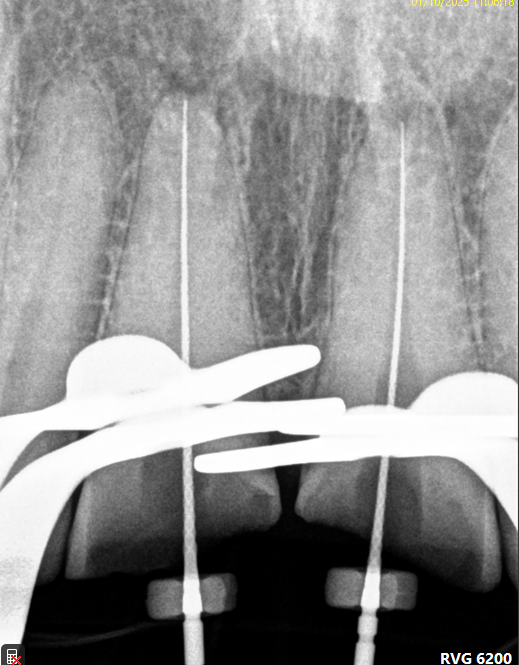

Case: RCT on Tooth #8

37-year-old female, healthy, no medications, no allergies.

Dx: Pulp necrosis and asymptomatic apical periodontitis with PARL

Tx: Non-surgical root canal therapy (RCT).

Reflection

Pulp stones were noted in #8 and neighboring teeth but did not complicate access. Minor sealer puff observed; given the biocompatibility of BC sealer, prognosis remains favorable. Awareness of sealer behavior is important for long-term outcomes.